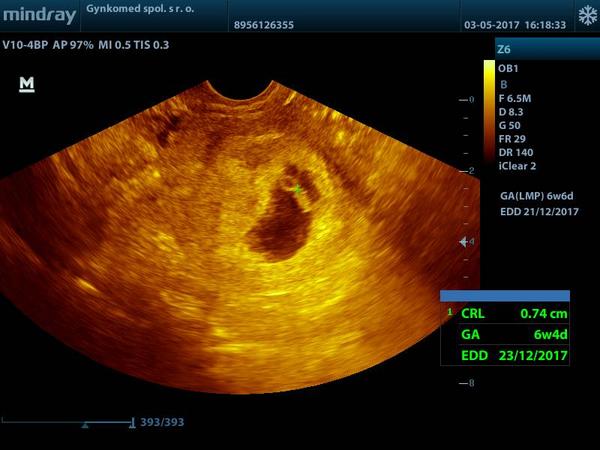

@nikuskaniki ja mam podobnu fotku - tiez je vidiet malicke babätko a placentu (akoby kruzok dole pod babätkom - to je placenta), no Ty si 6tt.+4, ja som bola vtedy az 8tt.+1...Kuk foto 😇

@nikuskaniki jeeeej nádherne babatko mojko..Dúfam že aj my dopadneme napodobne 😉áno dnes sme na rade a už sa budím či nezaspim 😝Tak pekne tehulkujte mojko a vážne zatiaľ máš termín 23.12. Budeme si písať s pôrodnice 😝